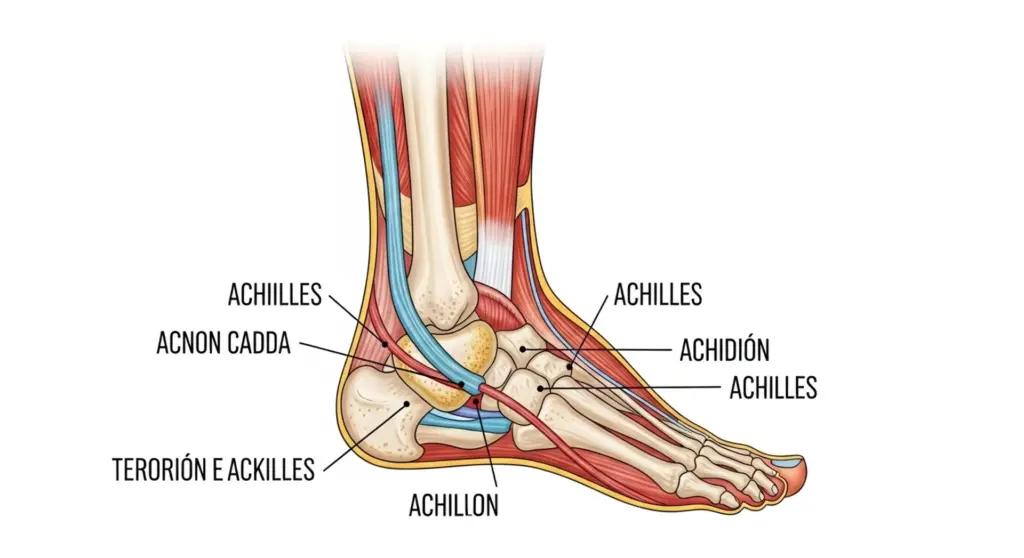

El tendón de Aquiles conecta los músculos de la pantorrilla (gastrocnemios o gemelos, y sóleo) con el hueso del talón (calcáneo). Con aproximadamente 15 cm de longitud y 6-7 mm de grosor, este tendón es fundamental para la marcha, la carrera y el salto. Cada vez que caminas, corres o saltas, este tendón transmite la fuerza de los músculos de la pantorrilla para producir el impulso necesario en el despegue del pie. La tendinitis de Aquiles se desarrolla cuando la demanda mecánica sobre el tendón supera su capacidad de recuperación y adaptación, produciendo inflamación, microdesgarros del tejido colágeno y dolor progresivo.

Existen dos tipos principales según la localización: la tendinitis insercional, que afecta a la zona donde el tendón se inserta en el calcáneo (últimos 2 cm del tendón) y representa el 20-25% de los casos, y la tendinitis no insercional o de la porción media, que afecta a la parte central del tendón (2-6 cm por encima de la inserción) y es más frecuente, representando el 75-80% de los casos. Cuando la inflamación se cronifica durante más de 6 semanas y aparece degeneración del tejido con cambios en su estructura y composición, hablamos de tendinopatía de Aquiles, una condición más seria que requiere tratamiento más prolongado.